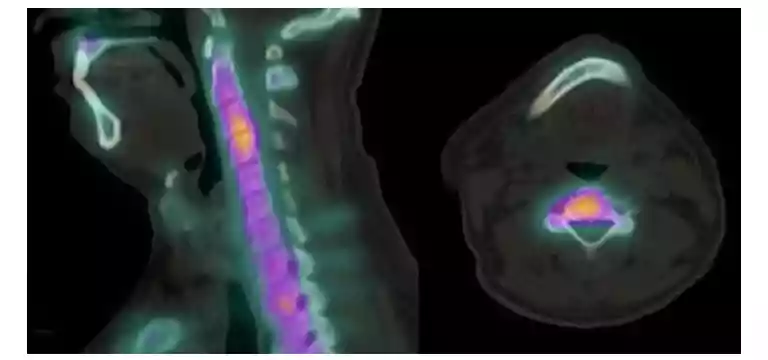

CT (computed tomography) scans, also known as CAT scans, utilize X-rays and advanced computer technology to produce detailed cross-sectional images of the body. The scanner rotates around the patient, capturing multiple X-ray images from different angles, which are then reconstructed into a 3D representation. This allows for a comprehensive evaluation of the internal structures and aids in precise preoperative planning.

Fusion of CT Scans with Other Imaging Modalities

By combining CT scans with other imaging modalities such as MRI, PET, or ultrasound, surgeons can gain a more comprehensive understanding of the patient's condition. This fusion of images enhances the visualization of different tissue characteristics and aids in precise surgical planning.